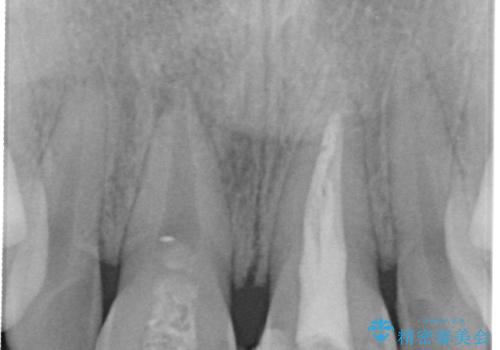

- 3週間後に迫った結婚式までになんとか前歯をきれいにしたいという希望で来院されました。

一回の治療時間を長く取り、限られた時間で最大限の結果を出せるよう集中治療を計画します。

ただ見えるクラウンを白くきれいにするのではなく、長期的な歯の予後を考えると根管治療・ファイバーコア築盛・精密な歯牙形成等クリアすべき条件は多々あると言えます。